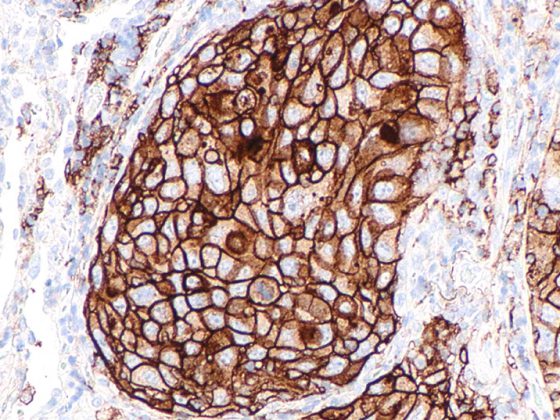

In einer post-hoc Analyse grosser randomisierter placebokontrollierter Studien wurden HbA1c sowie Körpergewicht und Blutdruck als Mediatorvariablen hinsichtlich der nierenschützenden Effekte der GLP-1-Rezeptoragonisten Semaglutid und Liraglutid bei Typ-2-Diabetes untersucht. Die Ergebnisse wurden am diesjährigen EASD Virtual Meeting präsentiert.